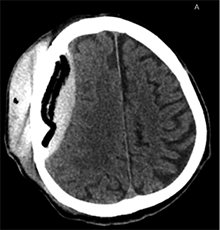

53 m. vyras sumuštas gatvėje ir greitosios medicinos pagalbos atvežtas į Priėmimo skyrių. Pacientui atlikta galvos kompiuterinė tomografija (GKT). Rasta: poūmė, stora, apie 16 mm dydžio subdurinė hematoma (SDH) dešinėje pusėje konveksitaliai ir ūmi nedidelė SDH kairėje pusėje frontoparietaliai. Vidurio struktūrų dislokacija (VSD) į kairę – minimali. Kairėje – kaukolės skliauto linijinis lūžis. Nustatyta nosies kaulų, nosies pertvaros, dešiniojo viršutinio žandikaulio kaktinės ataugos ir kūno, sinuso sienelių lūžių, dešinės akiduobės medialinio krašto lūžių ir dešiniojo skruostinio lanko lūžių (1 pav.). 2020 m. liepos mėn. pacientas skubos tvarka operuotas: atlikta dešinė kraniotomija, pašalinta hematoma. Atlikus kontrolinę GKT, buvo matyti, kad pašalinta didžioji hematomos dalis (2 pav.). Pacientas konsultuotas veido ir žandikaulio chirurgo, skubus chirurginis gydymas neindikuotas. Praėjus 3 savaitėms, pacientas, esant gerai funkcinei ir neurologinei būklei, tolesnio gydymo perkeltas į slaugos ligoninę, vėliau išleistas gydytis ambulatoriškai.

2 pav. Po pirmosios operacijos (didžioji hematomos dalis pašalinta, VSD be dislokacijos)